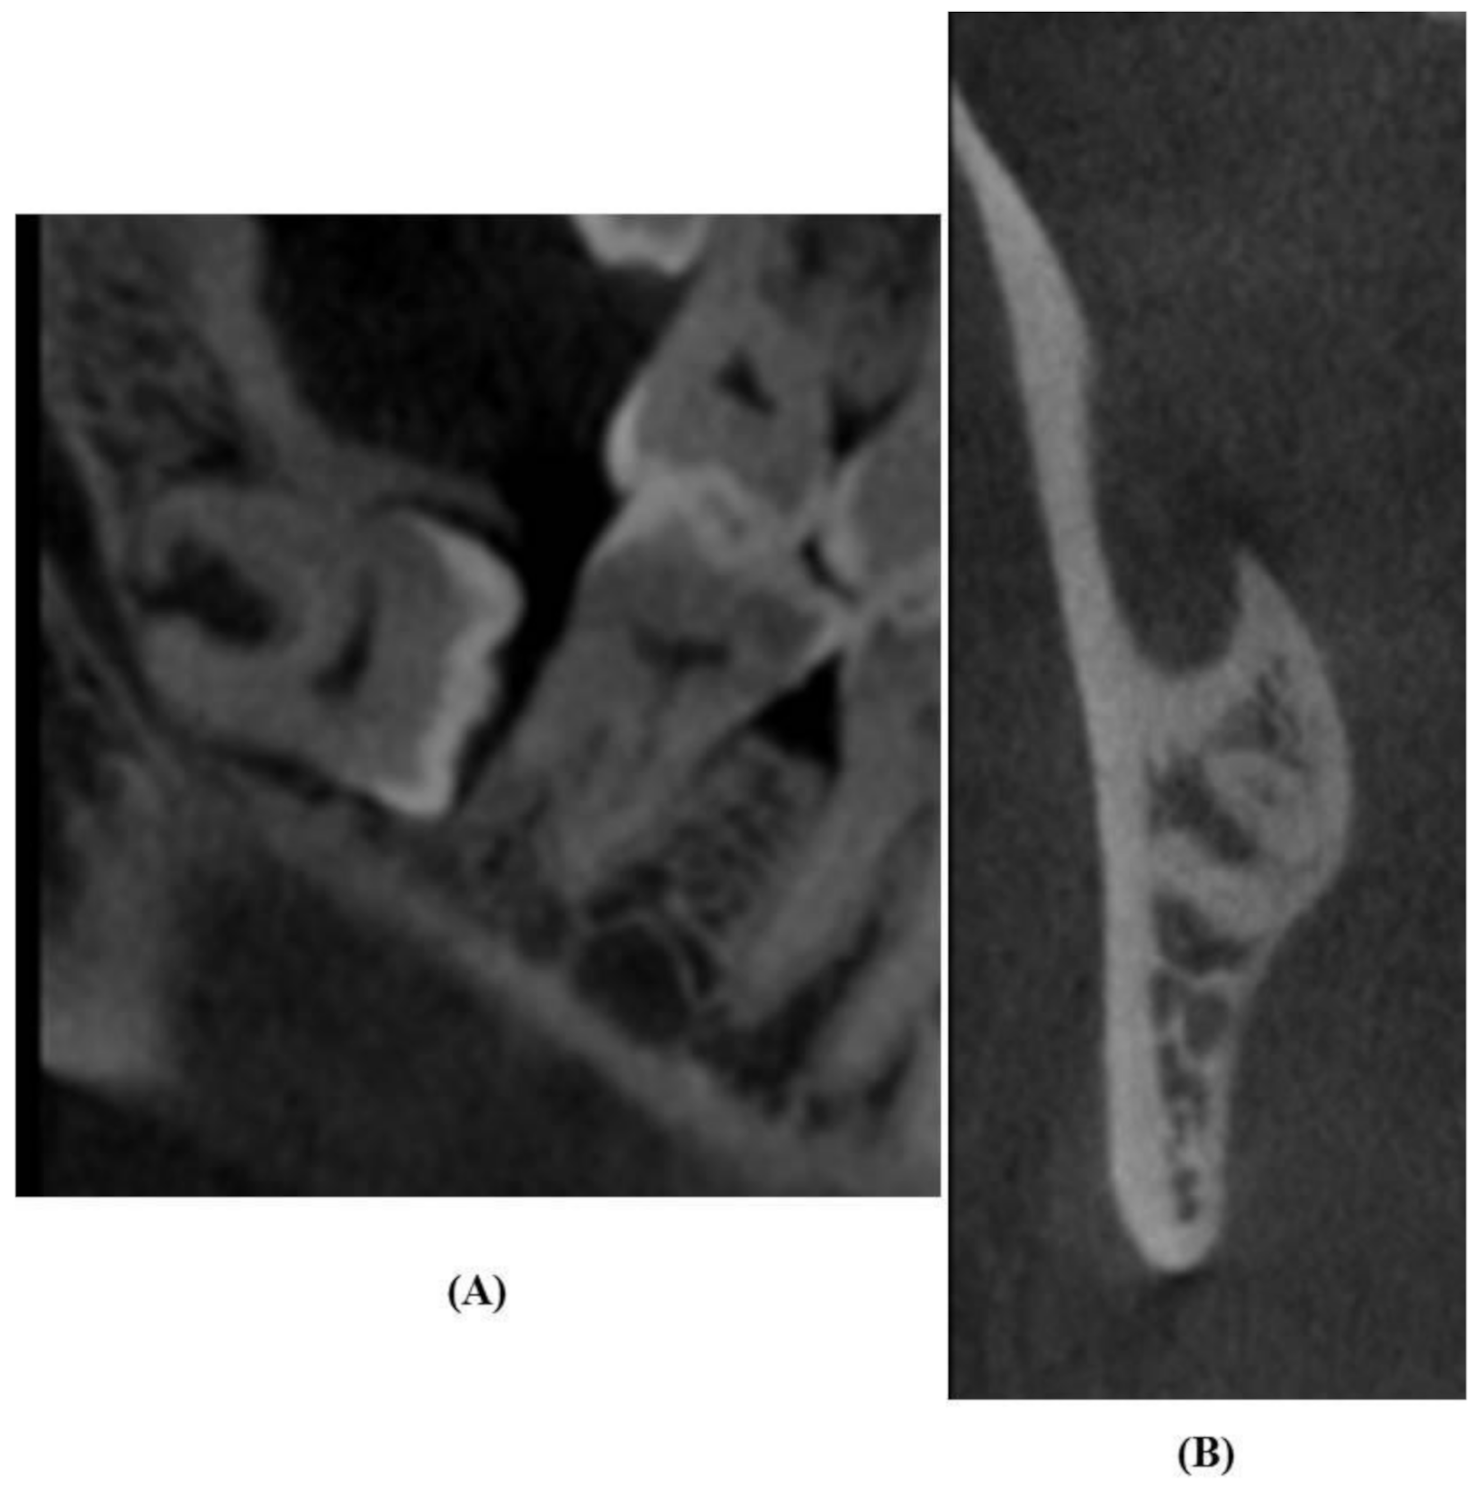

2.4. Evaluation of OPG Images

2.5. Analysis of CBCT Images